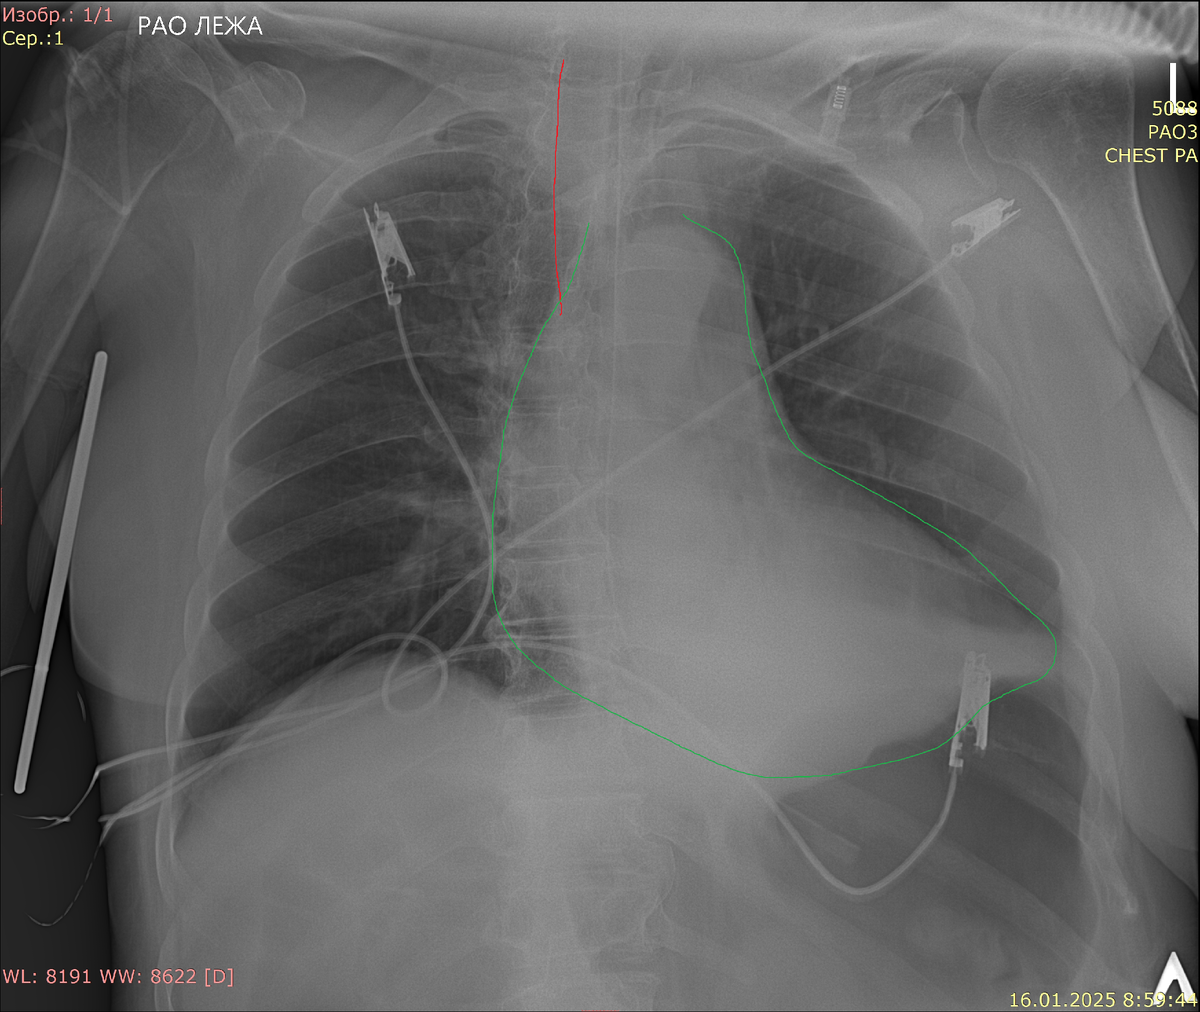

На рентгеновских снимках ЦВК визуализируются как тонкие линейные структуры, которые могут проходить от места введения (например, яремной или подключичной вены) до правого предсердия, где они должны правильно размещаться для обеспечения оптимального функционирования. Ключевыми аспектами, на которые врачи обращают внимание при интерпретации рентгенограмм, являются:

1. Положение катетера: Идеальное расположение ЦВК синдрома осуществляется вблизи передней стенки правого предсердия. Рентгенограмма позволяет врачу убедиться, что кончик катетера находится в правильной области, что минимизирует риск тромбообразования и травмирования сосудов.

3. Поиск осложнений: При изучении рентгенограмм можно выявить потенциальные осложнения, такие как пневмоторакс, который может возникнуть в результате травмы легких, или возможные крошечные воздушные эмболии, попадающие в венозное русло. Визуализируя органы, такие как легкие, врачи могут обнаружить аномалии, указывающие на необходимость немедленного вмешательства.